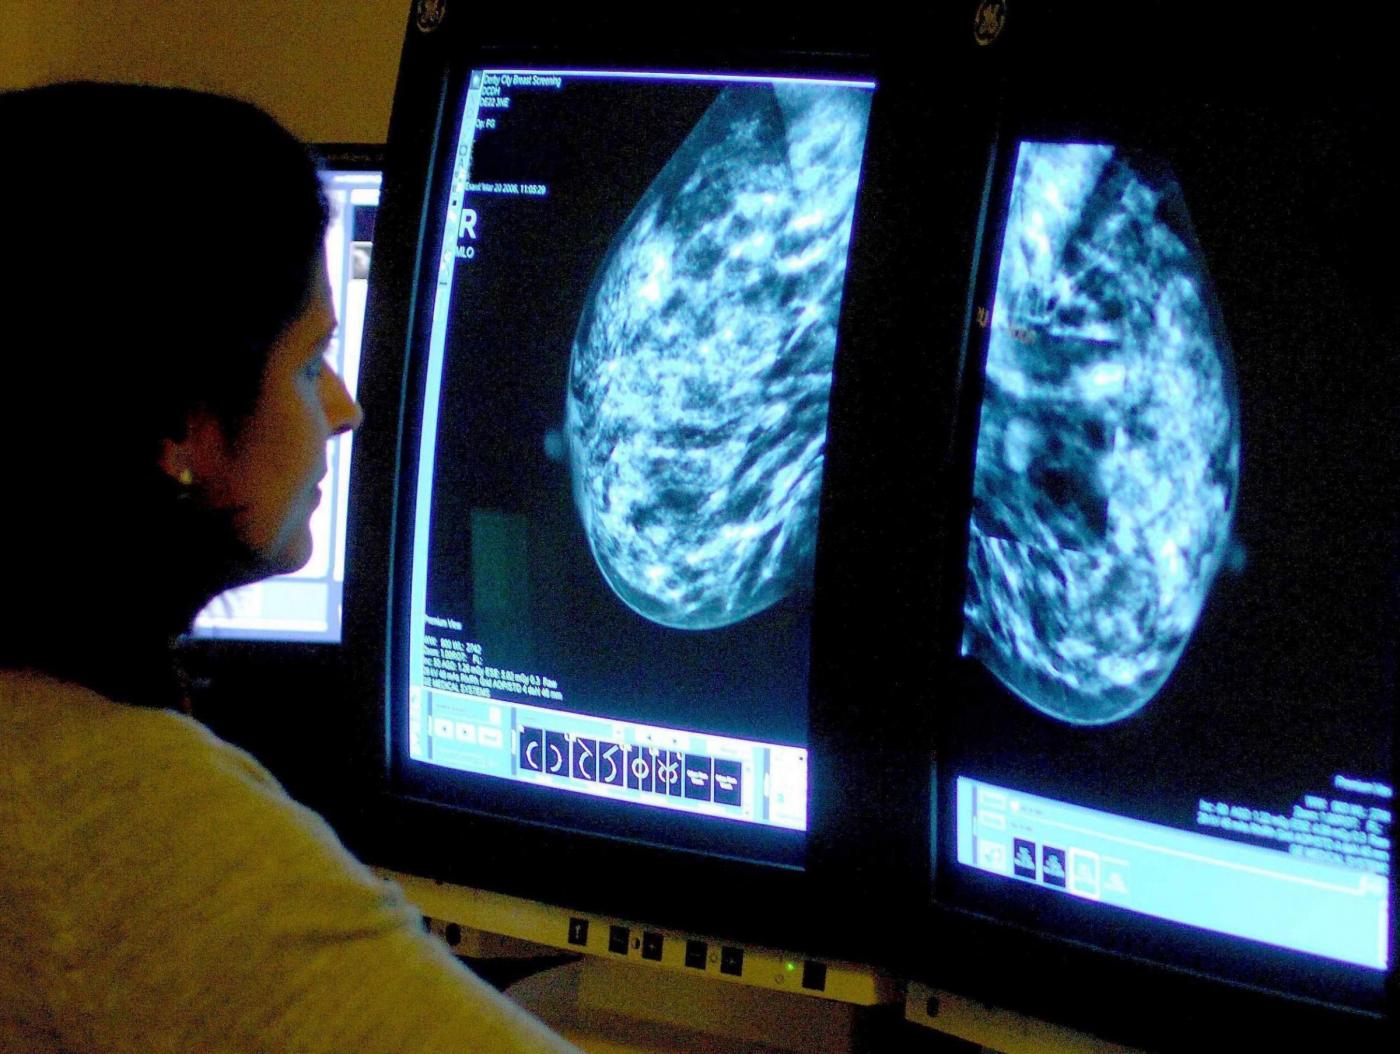

Visite al seno gratuite? C’è ancora tempo. Passato marzo, anche nei mesi diaprile e maggio il consiglio è di segnarvi un appuntamento importante con la prevenzione del tumore al seno. In occasione di questi giorni dedicati all’evento ‘Prevenzione Donna‘, durante i week end sarà possibile sottoporsi a visite al seno gratis e a screening di controllo di gratuiti che hanno chiaramente lo scopo di individuare o escludere una patologia senologica. La diagnosi precoce, come ben sappiamo, è molto importante per tutelare la salute delle donna, anche delle più giovani. Ecco il programma con le date delle visite al seno gratis.